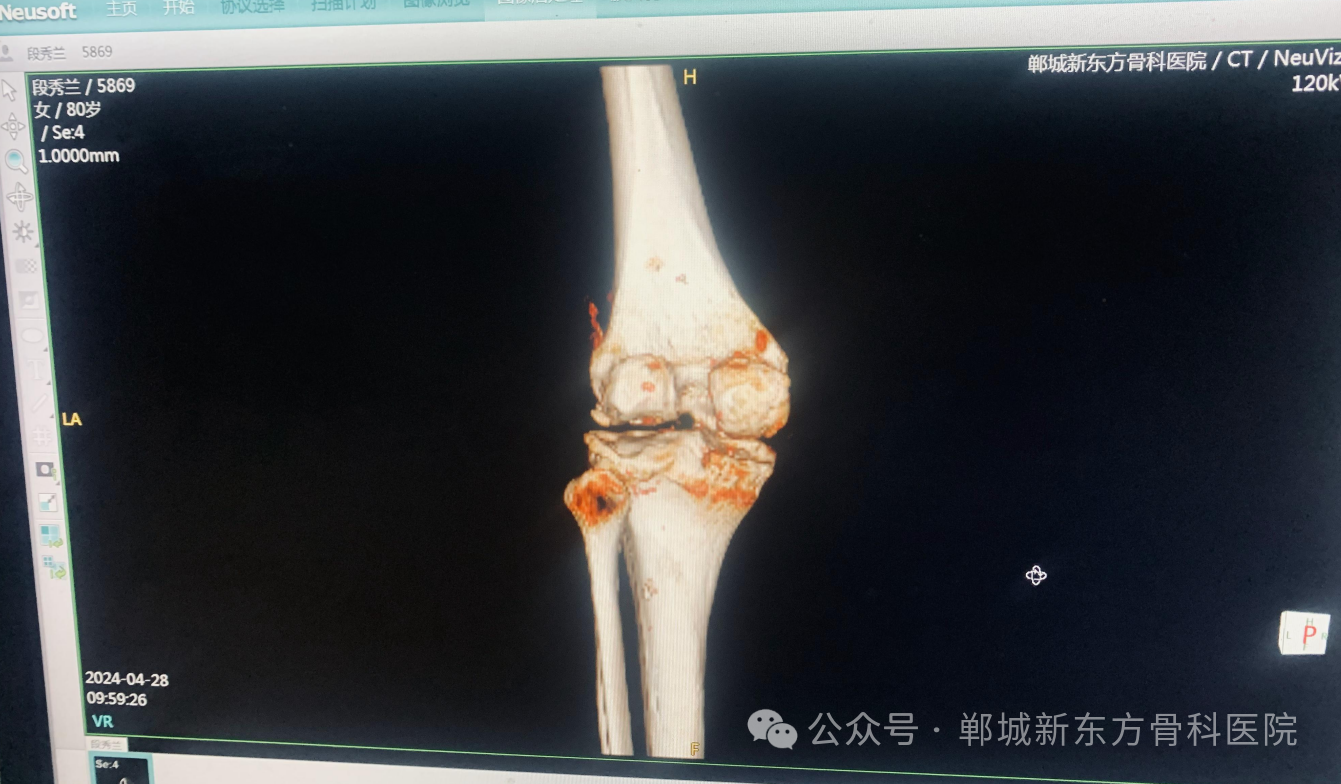

在郸城新东方骨科医院,我们深信,每一个生命都值得被尊重与呵护,尤其对于五保户“段秀兰”这样的社会弱势群体。近期,我们有幸为一位五保户膝关节疾病患者提供了专业治疗,虽然治疗本身是有偿服务,但医院秉承人文关怀精神,通过一系列优惠政策和爱心援助,确保了患者能够得到必要且高质量的医疗服务。

考虑到五保户的特殊情况,“郸城新东方骨科医院”特别为该患者定制了经济援助方案,大幅度减免了治疗费用,包括膝关节置换手术费、住院费及相关检查费用。我们深知,经济压力不应成为康复之路上的障碍,因此,通过医院内部的支持,最大化地减轻了患者的经济负担。为患者“段秀兰”重塑健康之路。

由资深骨科专家领导的医疗团队,运用最先进的医疗技术和个性化治疗方案,确保手术安全、高效。从精准的术前评估到细致的术后护理,每一步都体现了医院的专业水平与对患者的人文关怀。